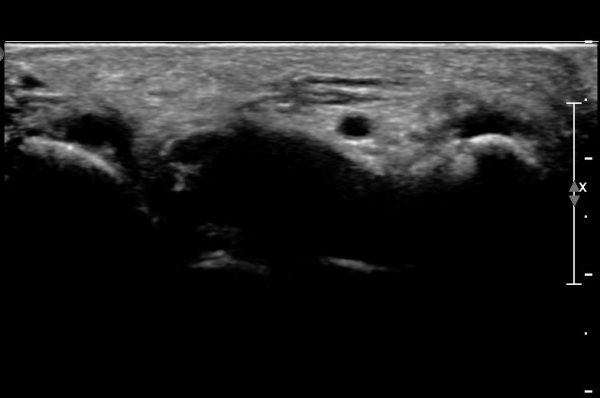

ÃÊÀ½ÆÄ°Ë»ç : ¼Õ¸ñ ¼ö±Ù°ü ±ÙÀ§ºÎ Ⱦ´Ü¸é°Ë»ç¿¡¼­ Äá¾Ë»À Ç¥ÃþÀ¸·Î ¾à°£ÀÇ ¿¬ºÎÁ¶Á÷ ºÎÁ¾ÀÌ °üÂûµÊ(»çÁø 1).